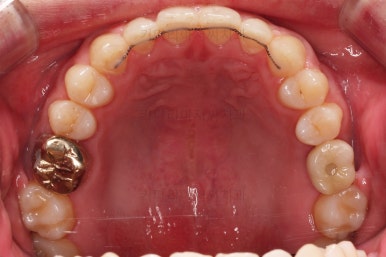

충치치료가 완료된 부위는 골드 크라운(금니)이 씌워졌어요.

임플란트를 하기에 적절한 사이즈로 공간은 맞춰줍니다.

거의 모습이 완성되었습니다.

교정치료도 종료 되었고 연산동임플란트 잘 완성이 되었어요.

총 14개월이 걸린 치료였는데 비교적 짧은 기간 내에 틈새도 모으고, 임플란트 및 충치치료도 다 완료를 할 수 있었습니다.